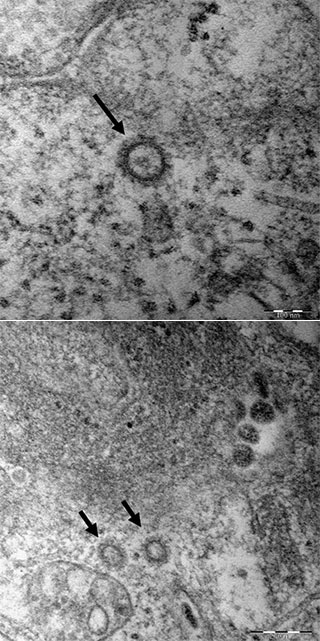

질병관리본부는 6명의 '코로나19' 환자로부터 얻은 바이러스의 고해상 전자현미경 사진을 공개했다.​ /사진= 질병관리본부 제공

코로나19 바이러스는 동그란 단백질 껍데기 안에 2만9800개 유전자 염기서열로 구성됐는데, 이 가운데 0.03%인 8~9개 일부 염기만 제외한 나머지는 국외 코로나19 환자의 유전자 염기서열과 동일했다. 코로나 바이러스는 단백질 껍데기 모양이 왕관처럼 생겨 이 같은 이름이 붙었다.